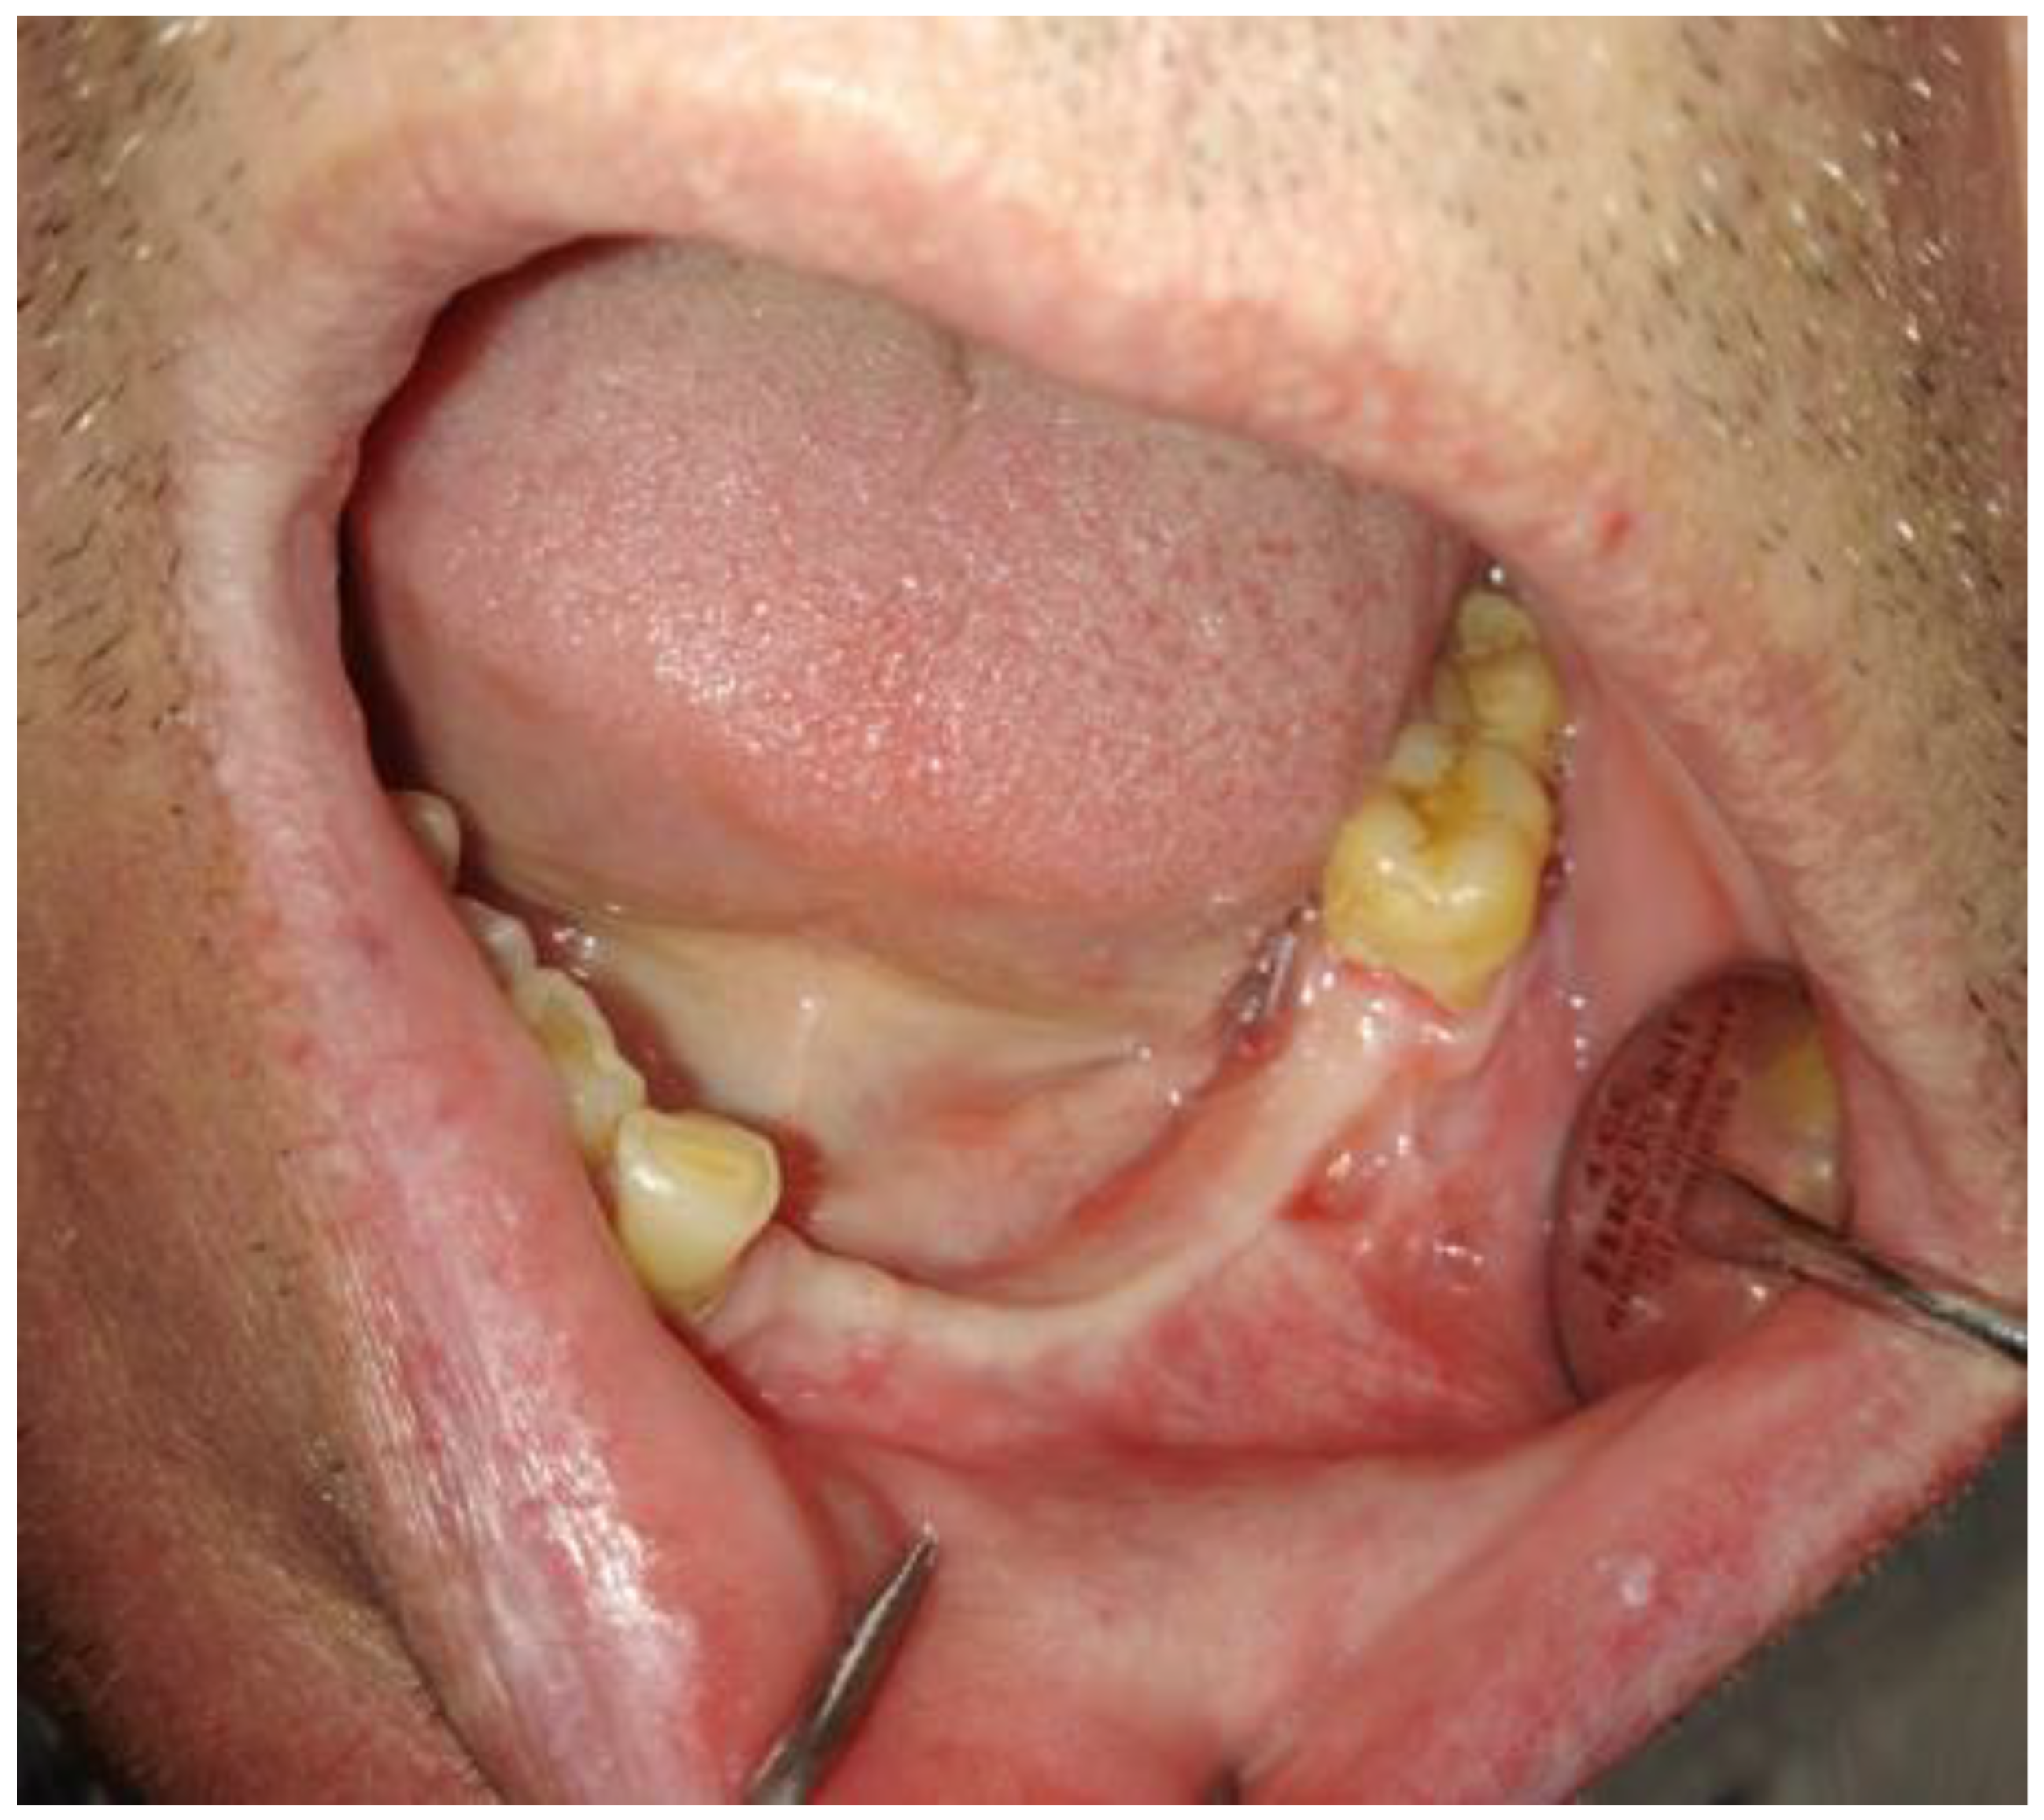

Further examination revealed extensive vestibular swelling ranging from teeth 32–35 and crepitation sign, followed by some elevation and fluctuation between teeth 33–34 (Figure 2). The mucosa was unaffected, and tenderness on the palpation was not noted. However, teeth 31–35 mobility was noted. Teeth 34 and 35 were treated endodontically by a local dentist because of the cyst. Teeth 33–43 remained vital and responsive to cold stimuli. There were no neurological deficiencies related to either cranial nerves or the trigeminal (no Vincent sign) or facial nerves (no palsy). The intraoral photograph reveals good hygiene, with some visible swelling in the anterior portion of the mandible (Figure 3 and Figure 4).

Figure 4. The scope of cystic lesion in CBCT.